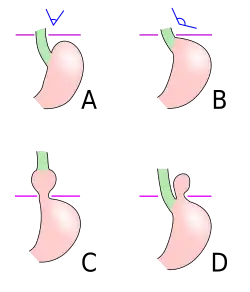

Four types of esophageal hiatal hernia are identified:[10]

Type I: A type I hernia, also known as a sliding hiatal hernia, occurs when part of the stomach slides up through the hiatal opening in the diaphragm.[11] There is a widening of the muscular hiatal tunnel and circumferential laxity of the phrenoesophageal ligament, allowing a portion of the gastric cardia to herniate upward into the posterior mediastinum. The clinical significance of type I hernias is in their association with reflux disease. Sliding hernias are the most common type and account for 95% of all hiatal hernias.[12] (C)

Type II: A type II hernia, also known as a paraesophageal or rolling hernia, occurs when the fundus and greater curvature of the stomach roll up through the diaphragm, forming a pocket alongside the esophagus.[11] It results from a localized defect in the phrenoesophageal ligament while the gastroesophageal junction remains fixed to the preaortic fascia and the median arcuate ligament. The gastric fundus then serves as the leading point of herniation. Although type II hernias are associated with reflux disease, their primary clinical significance lies in the potential for mechanical complications. (D)

Type III: Type III hernias have elements of both types I and II hernias. With progressive enlargement of the hernia through the hiatus, the phrenoesophageal ligament stretches, displacing the gastroesophageal junction above the diaphragm, thereby adding a sliding element to the type II hernia.

Type IV: Type IV hiatus hernia is associated with a large defect in the phrenoesophageal ligament, allowing other organs, such as the colon, spleen, pancreas, and small intestine to enter the hernia sac.

The end stage of type I and type II hernias occurs when the whole stomach migrates up into the chest by rotating 180° around its longitudinal axis, with the cardia and pylorus as fixed points. In this situation, the abnormality is usually referred to as an intrathoracic stomach.